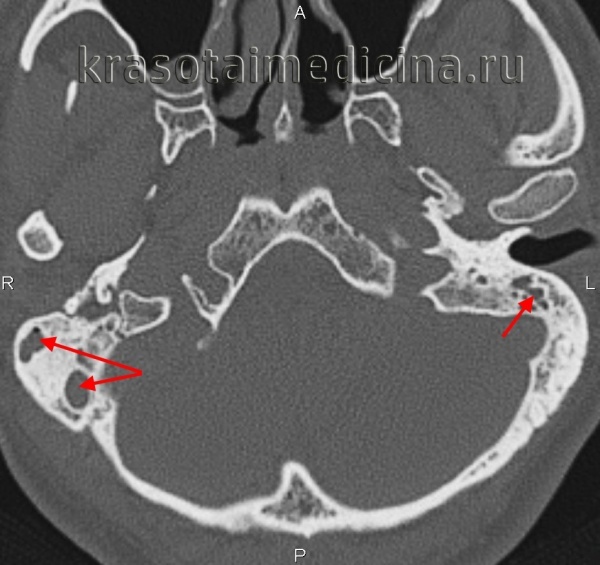

- Комп’ютерної томографії черепа – використовується для перегляду зображення поперечного перерізу по горизонталі і вертикалі. КТ показує детальні зображення будь-якої частини тіла, в тому числі кісток, м’язів, жиру і органів.

Комп’ютерна томографія – стандартний метод, за допомогою якого діагностують мастоїдит. Що це таке? Даний вид діагностики дозволяє чітко розглянути всі структури черепа і оцінити масштаби розвитку гнійних процесів та їх дальність від головного мозку і лицьового нерва.

Ця методика заснована на поетапному дослідженні структури будь-якого об’єкта – порівнюється ефект впливу рентгенівського випромінювання на відмінні по щільності тканини. Отримані дані піддаються складній комп’ютерній обробці.

наприклад, допомагає виявити нечітко помітні перегородки осередків в результаті запального процесу, що явно свідчить про розвиток мастоидита. Крім того, при підозрах на мастоїдит, проводять клінічний аналіз крові і гною з вуха на чутливість до антибіотиків.